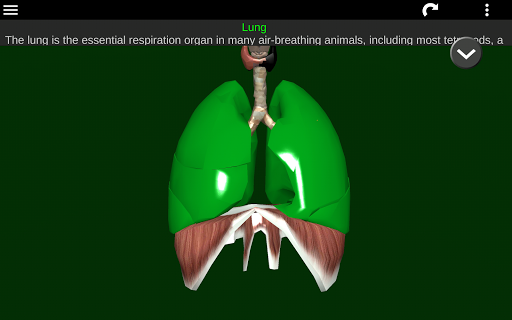

* Respiratory system, which includes the trachea, bronchi, lungs and an animation of this system.